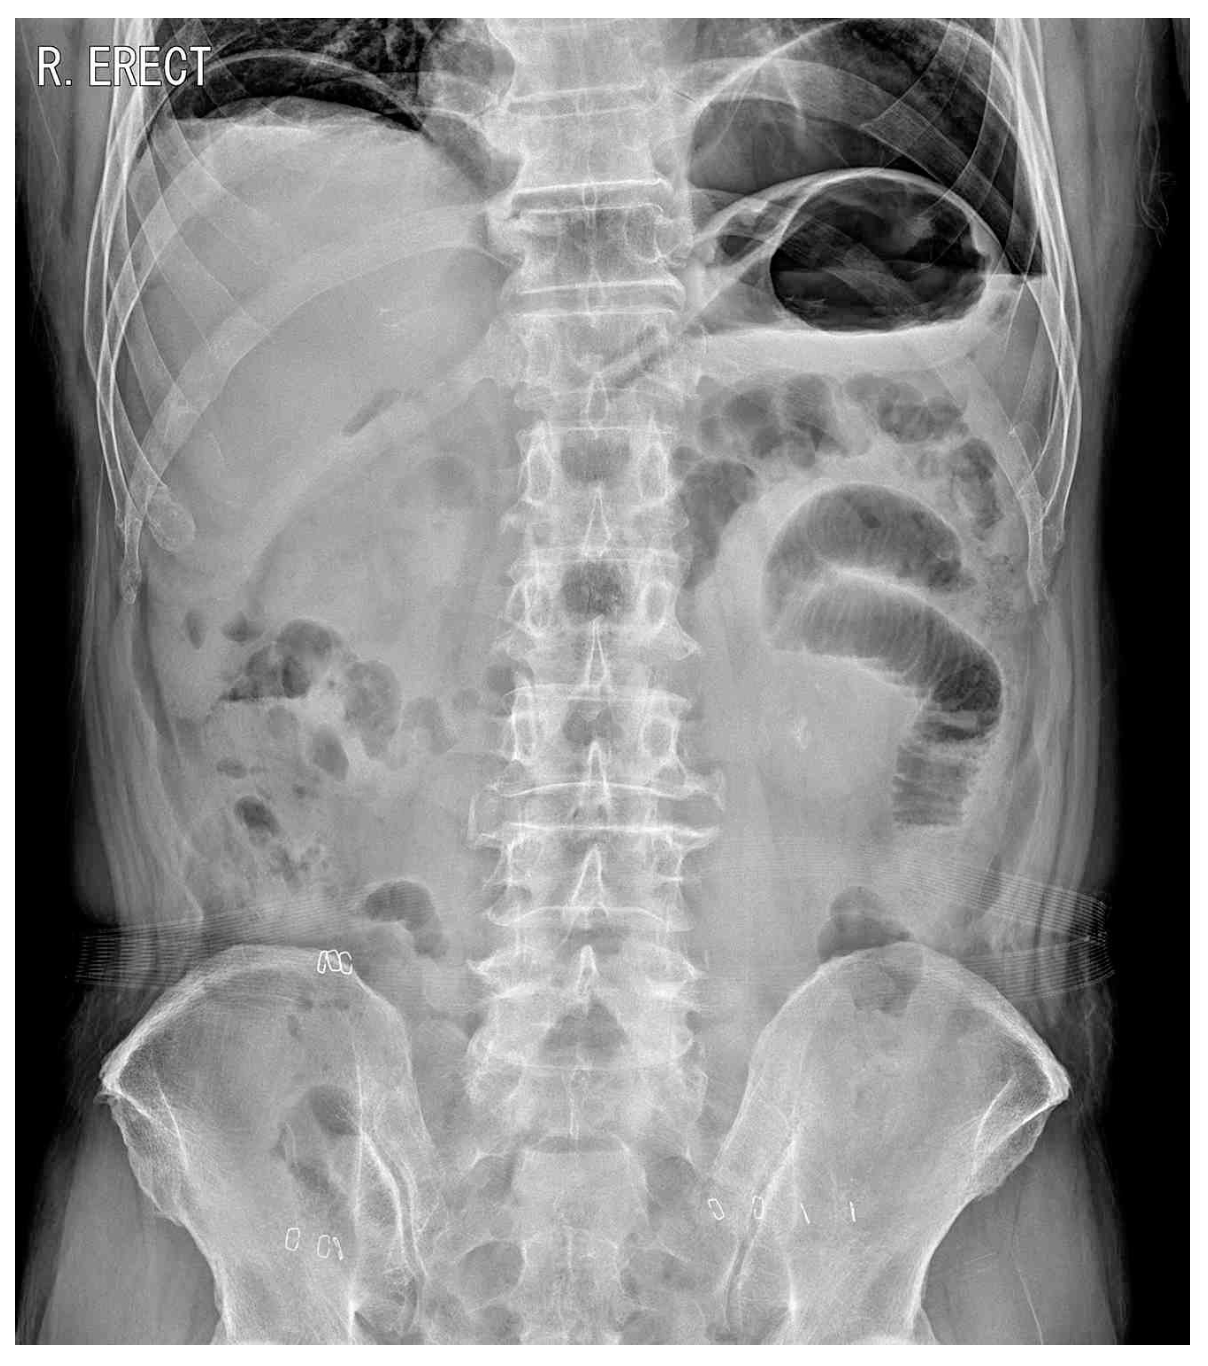

65세 남자가 구불결장암으로 복강경 전방절제를 받고 입원 중이다. 수술 후 5일째 아침부터 아랫배가 심하게 아프다고 한다. 통증은 2시간 전부터 시작되었고, 점점 더 심해진다고 한다. 혈압 90/55 mmHg, 맥박 105회/분, 호흡 24회/분, 체온 38.3°C이다. 배는 조금 불러있고 아랫배에 압통과 반동압통이 있다. 혈액검사 결과는 다음과 같다. 수술 후 4일째 복부 X선사진과 5일째 복부 X선사진이다. 처치는?

CXR(POD#4): No free air

• 위장관 천공이 의심되는 경우 CXR을 통해 빠르게 천공 여부를 평가해야 한다. 수술 4일차에는 천공 소견이 없었으나, 증상이 시작된 5일차 흉부 X선 검사에서 횡격막 아래 공기가 관찰되었으며, 이는 수술 부위 천공과 이로 인한 범복막염을 강하게 시사한다.

• 복강경 수술을 할 때는 시야 확보 등을 위해 복강 내 CO2 등의 가스를 주입하며, 따라서 수술 후에는 정상적으로 pneumoperitoneum이 관찰될 수 있다. 단, 본 증례는 수술로 인해 유입된 가스가 POD 4일차에 전부 흡수되었음이 확인된 이후 다시 POD 5일차에 pneumoperitoneum이 생긴 것이므로 이상 소견이 맞다.